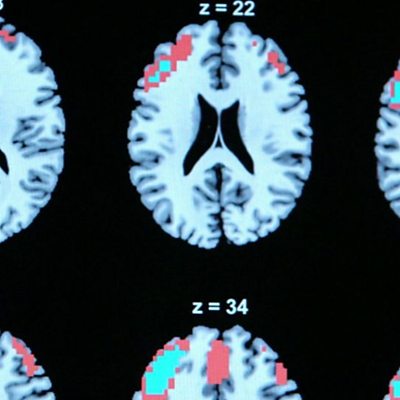

'I didn't consent to being locked up or the medication'

More than 100 people are considering legal action against the NHS after having ECT.